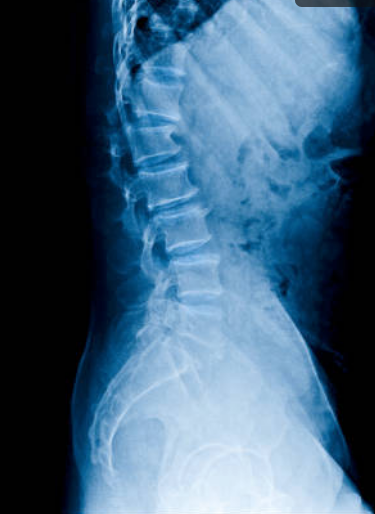

Se trata de una intervención quirúrgica en la que se fijan dos piezas óseas, anclando una articulación. Está indicado cuando hay inestabilidad vertebral.

Procesos tales como espondilolistesis lumbares; escoliosis degenerativas; patología traumática con fracturas y algunos casos de raquiestenosis lumbar.

Cirugías con abordajes microquirúrgicos anteriores o posteriores en función de la patología de base del enfermo.

Los abordajes cervicales anteriores con prótesis de titanio y miniplacas están indicados en enfermedades degenerativas discales extensas con osteofitosis que condiciona estenosis de canal central y foraminal; listesis cervicales degenerativas; patología traumática cervical que condicione inestabilidad o fracturas vertebrales.

Los abordajes posteriores con tornillos y barras se utilizan principalmente en casos de luxaciones atloaxoideas secundarias a artritis reumatoide y en algunos procesos traumáticos.